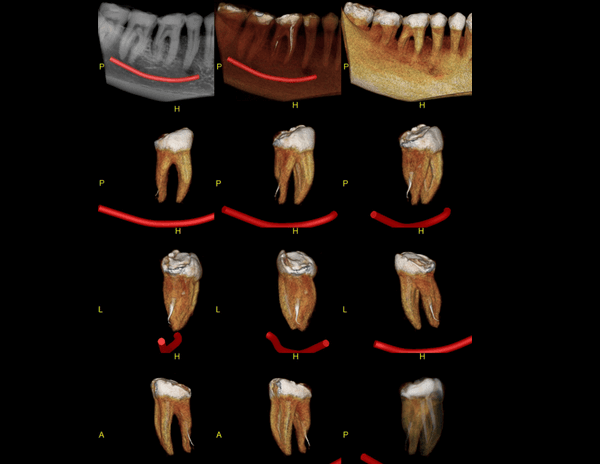

A Tomografia Computadorizada pela técnica do feixe cônico/cone beam (CBCT) introduziu um novo conceito de tomografia computadorizada na região bucomaxilofacial, que por meio da rápida aquisição volumétrica produz imagens com altíssimo grau de definição e fidelidade, além da redução na dose total de radiação emitida ao paciente.

Além disso, ocorre a minimização dos artefatos de imagem em relação à TC médica, o que torna possível a realização de imagens com qualidade diagnóstica e precisão sub-milimétrica, mesmo na presença de estruturas metálicas (restaurações, pinos/núcleos, aparelhos ortodônticos).